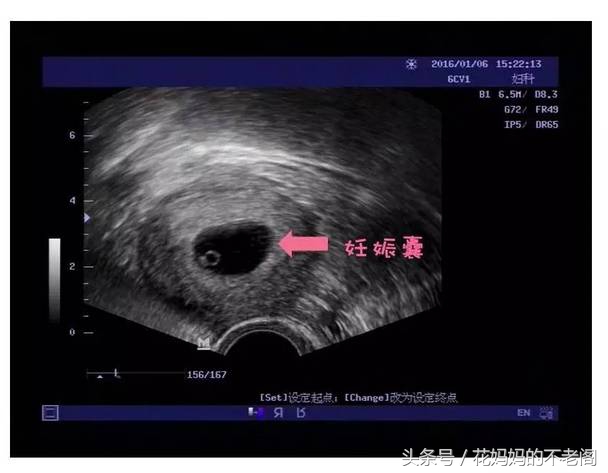

要确诊早期的宫内妊娠呢,要做一个超声检查,黑色的囊状结构-妊娠囊,戒指样结构-卵黄囊,超声检查可以在宫腔内探及胚胎的心跳,这个时候呢,确诊早孕,就可以去医院建立孕产妇保健手册了,一般建议12周以内完成(从最后一次月经的第一天开始算起)。